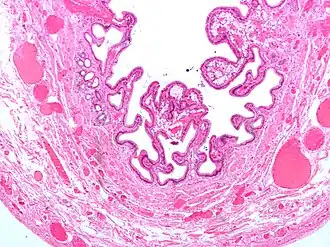

![]() Микрофотография жёлчного пузыря при холецистите и холестерозе | |